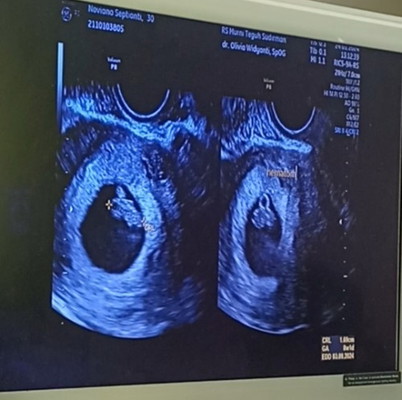

Hai bund, disini ada yang pernah mengalami Hematom(pembekuan darah) saat hamil muda ga ya?

wah saya mba hematom sch sekitar 5% dua minggu lalu di 6w1d, disruh 2 minggu lagi observasi. doain ya bund hr minggu ini hematomnya hilang. sejauh ini alhamdulillah gaada flek sama sekali cuman tetep aja takut๐ฅฒ